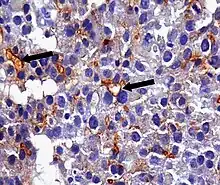

An anti-CEA antibody is an antibody against CEA. Such antibodies to CEA are commonly used in immunohistochemistry to identify cells expressing the glycoprotein in tissue samples. In adults, CEA is primarily expressed in cells of tumors (some malignant, some benign) [20] but they are particularly associated with the adenocarcinomas, such as those arising in the colon, lung, breast, stomach, or pancreas. It can therefore be used to distinguish between these and other similar cancers. For example, it can help to distinguish between adenocarcinoma of the lung and mesothelioma, a different type of lung cancer which is not normally CEA positive. Because even monoclonal antibodies to CEA tend to have some degree of cross-reactivity, occasionally giving false positive results, it is commonly employed in combination with other immunohistochemistry tests, such as those for BerEp4, WT1, and calretinin.[21] For cancers that highly express CEA, targeting CEA through radioimmunotherapy is one of the therapy approaches.[22] Engineered antibodies such as single-chain Fv antibodies (sFvs) or bispecific antibodies have been used for targeting and therapy of CEA expressing tumors both in vitro and in vivo with promising results [23][24] Regions of high CEA levels in the body can be detected with the monoclonal antibody arcitumomab.[25]